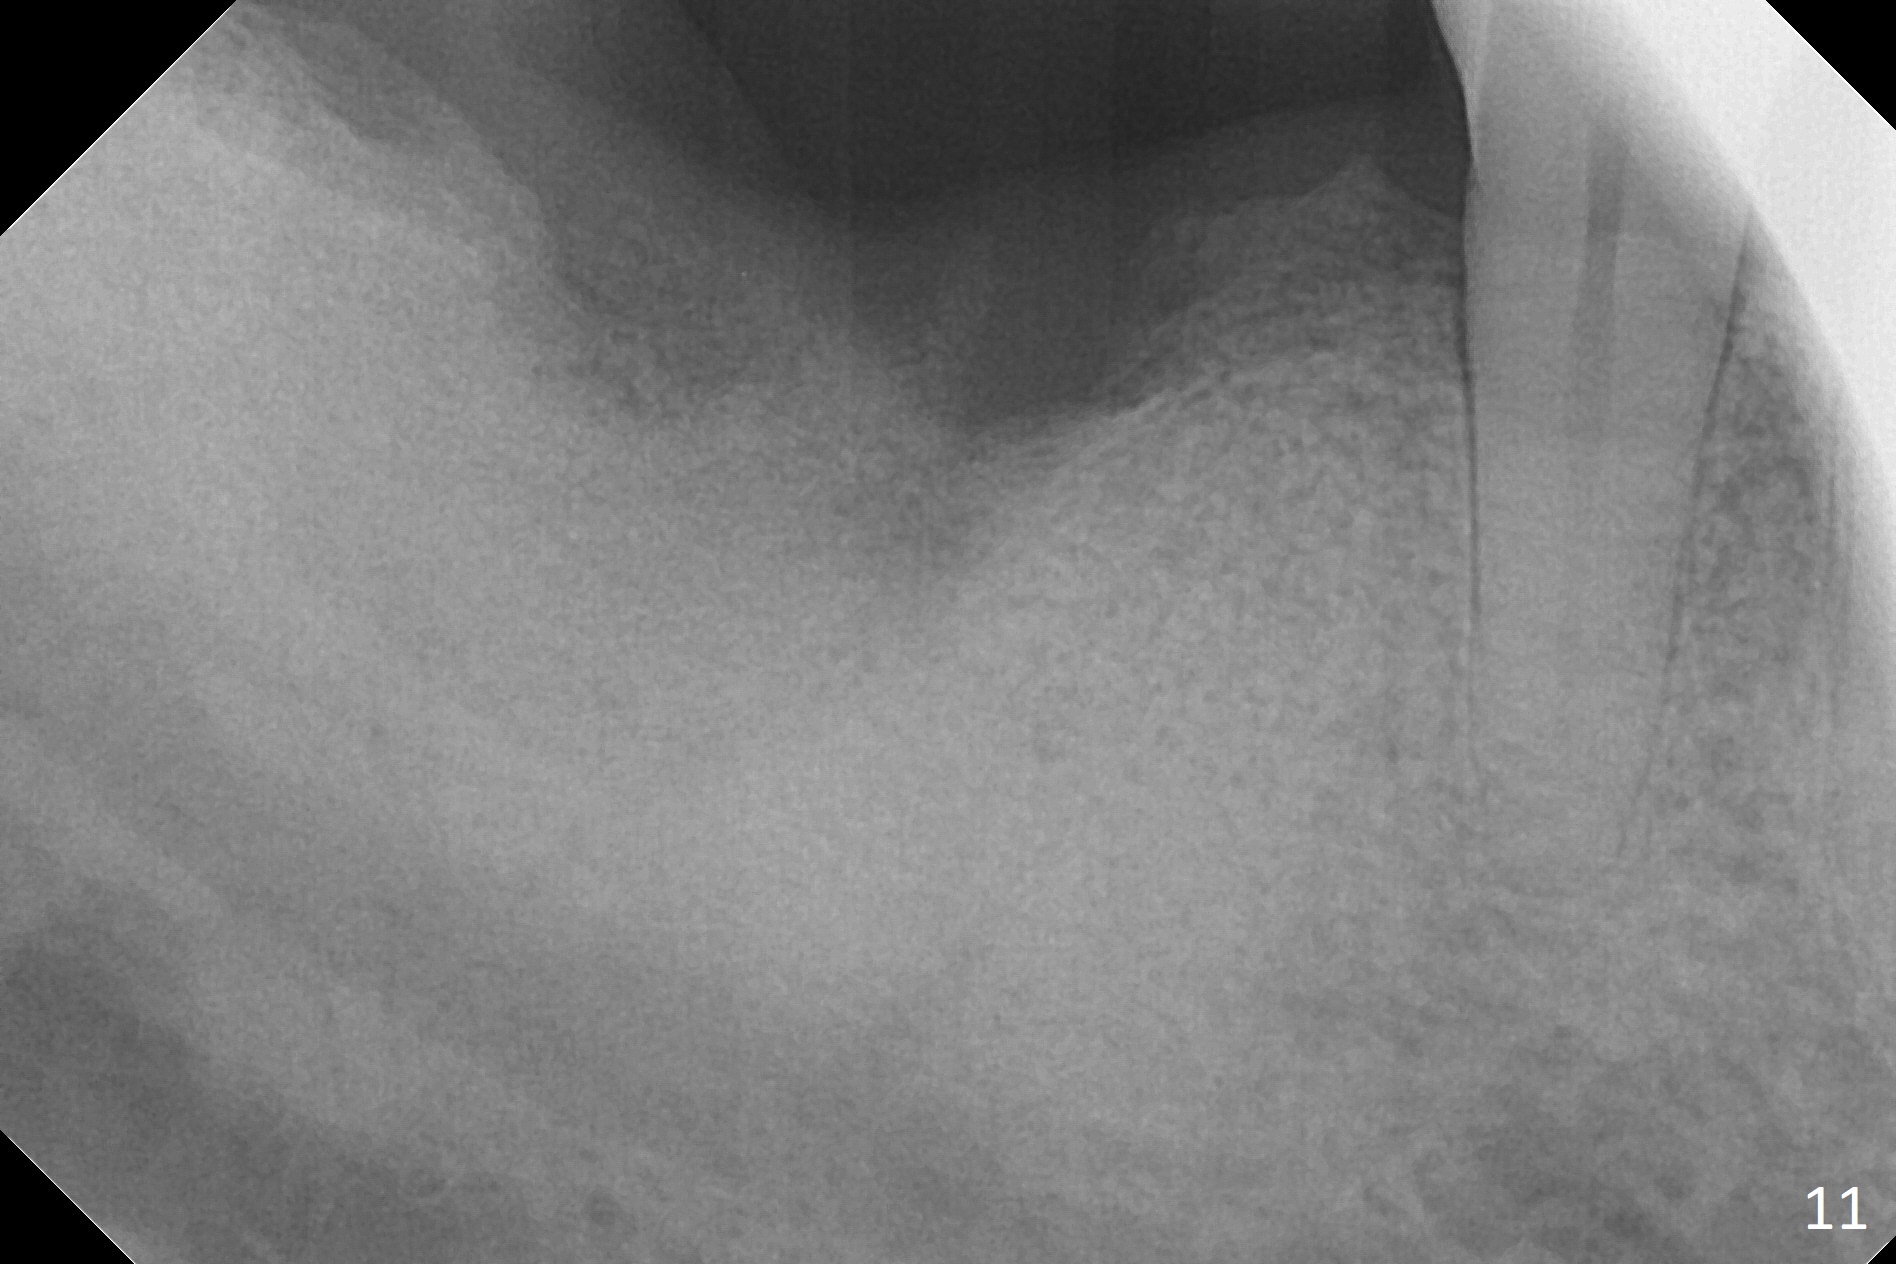

Extraction of the mobile tooth #31 (Fig.1) and debridement of the large socket are not difficult. But making osteotomy buccally does not seem to be easy. It will be difficult to restore. Instead, socket preservation is accomplished by filling the socket with approximately 1.5 cc of Mineralized Cortical/Cancellous allograft until the crest (Fig.2,5). The socket opening is closed by insertion of 4 pieces of PRF membranes (Fig.3) and 4-0 Chromic gut sutures (Fig.4). In the end of surgery, it appears that osteotomy in the center of the socket could be a better approach. Postop re-analysis of CT (Fig.6) and PA (Fig.7) shows that there is 3.9 mm of the native bone to support a 5.5x10 mm implant. Sinus Lift Master Kit should be used with 2 mm initial drill and 2.8 and 3.6 mm round drills with 4 mm stopper.